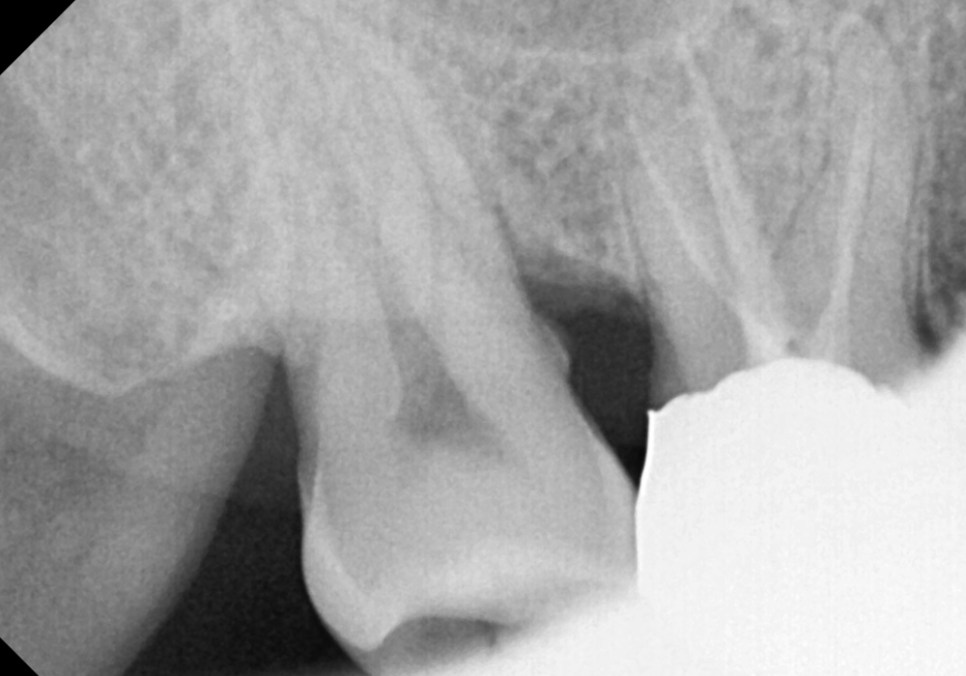

통증이 완전히 사라진 것을 확인한 뒤,

깨끗해진 신경관 안을 생체 친화적인 재료로

단단하게 채워 넣었습니다.

그리고 금이 간 치아가

더 이상 벌어지거나 깨지지 않도록

치아 전체를 감싸주는

크라운 치료를 진행했습니다.

240305

균열이 있는 치아는 크라운으로

단단하게 잡아주는 보강 작업이

무엇보다 중요합니다.